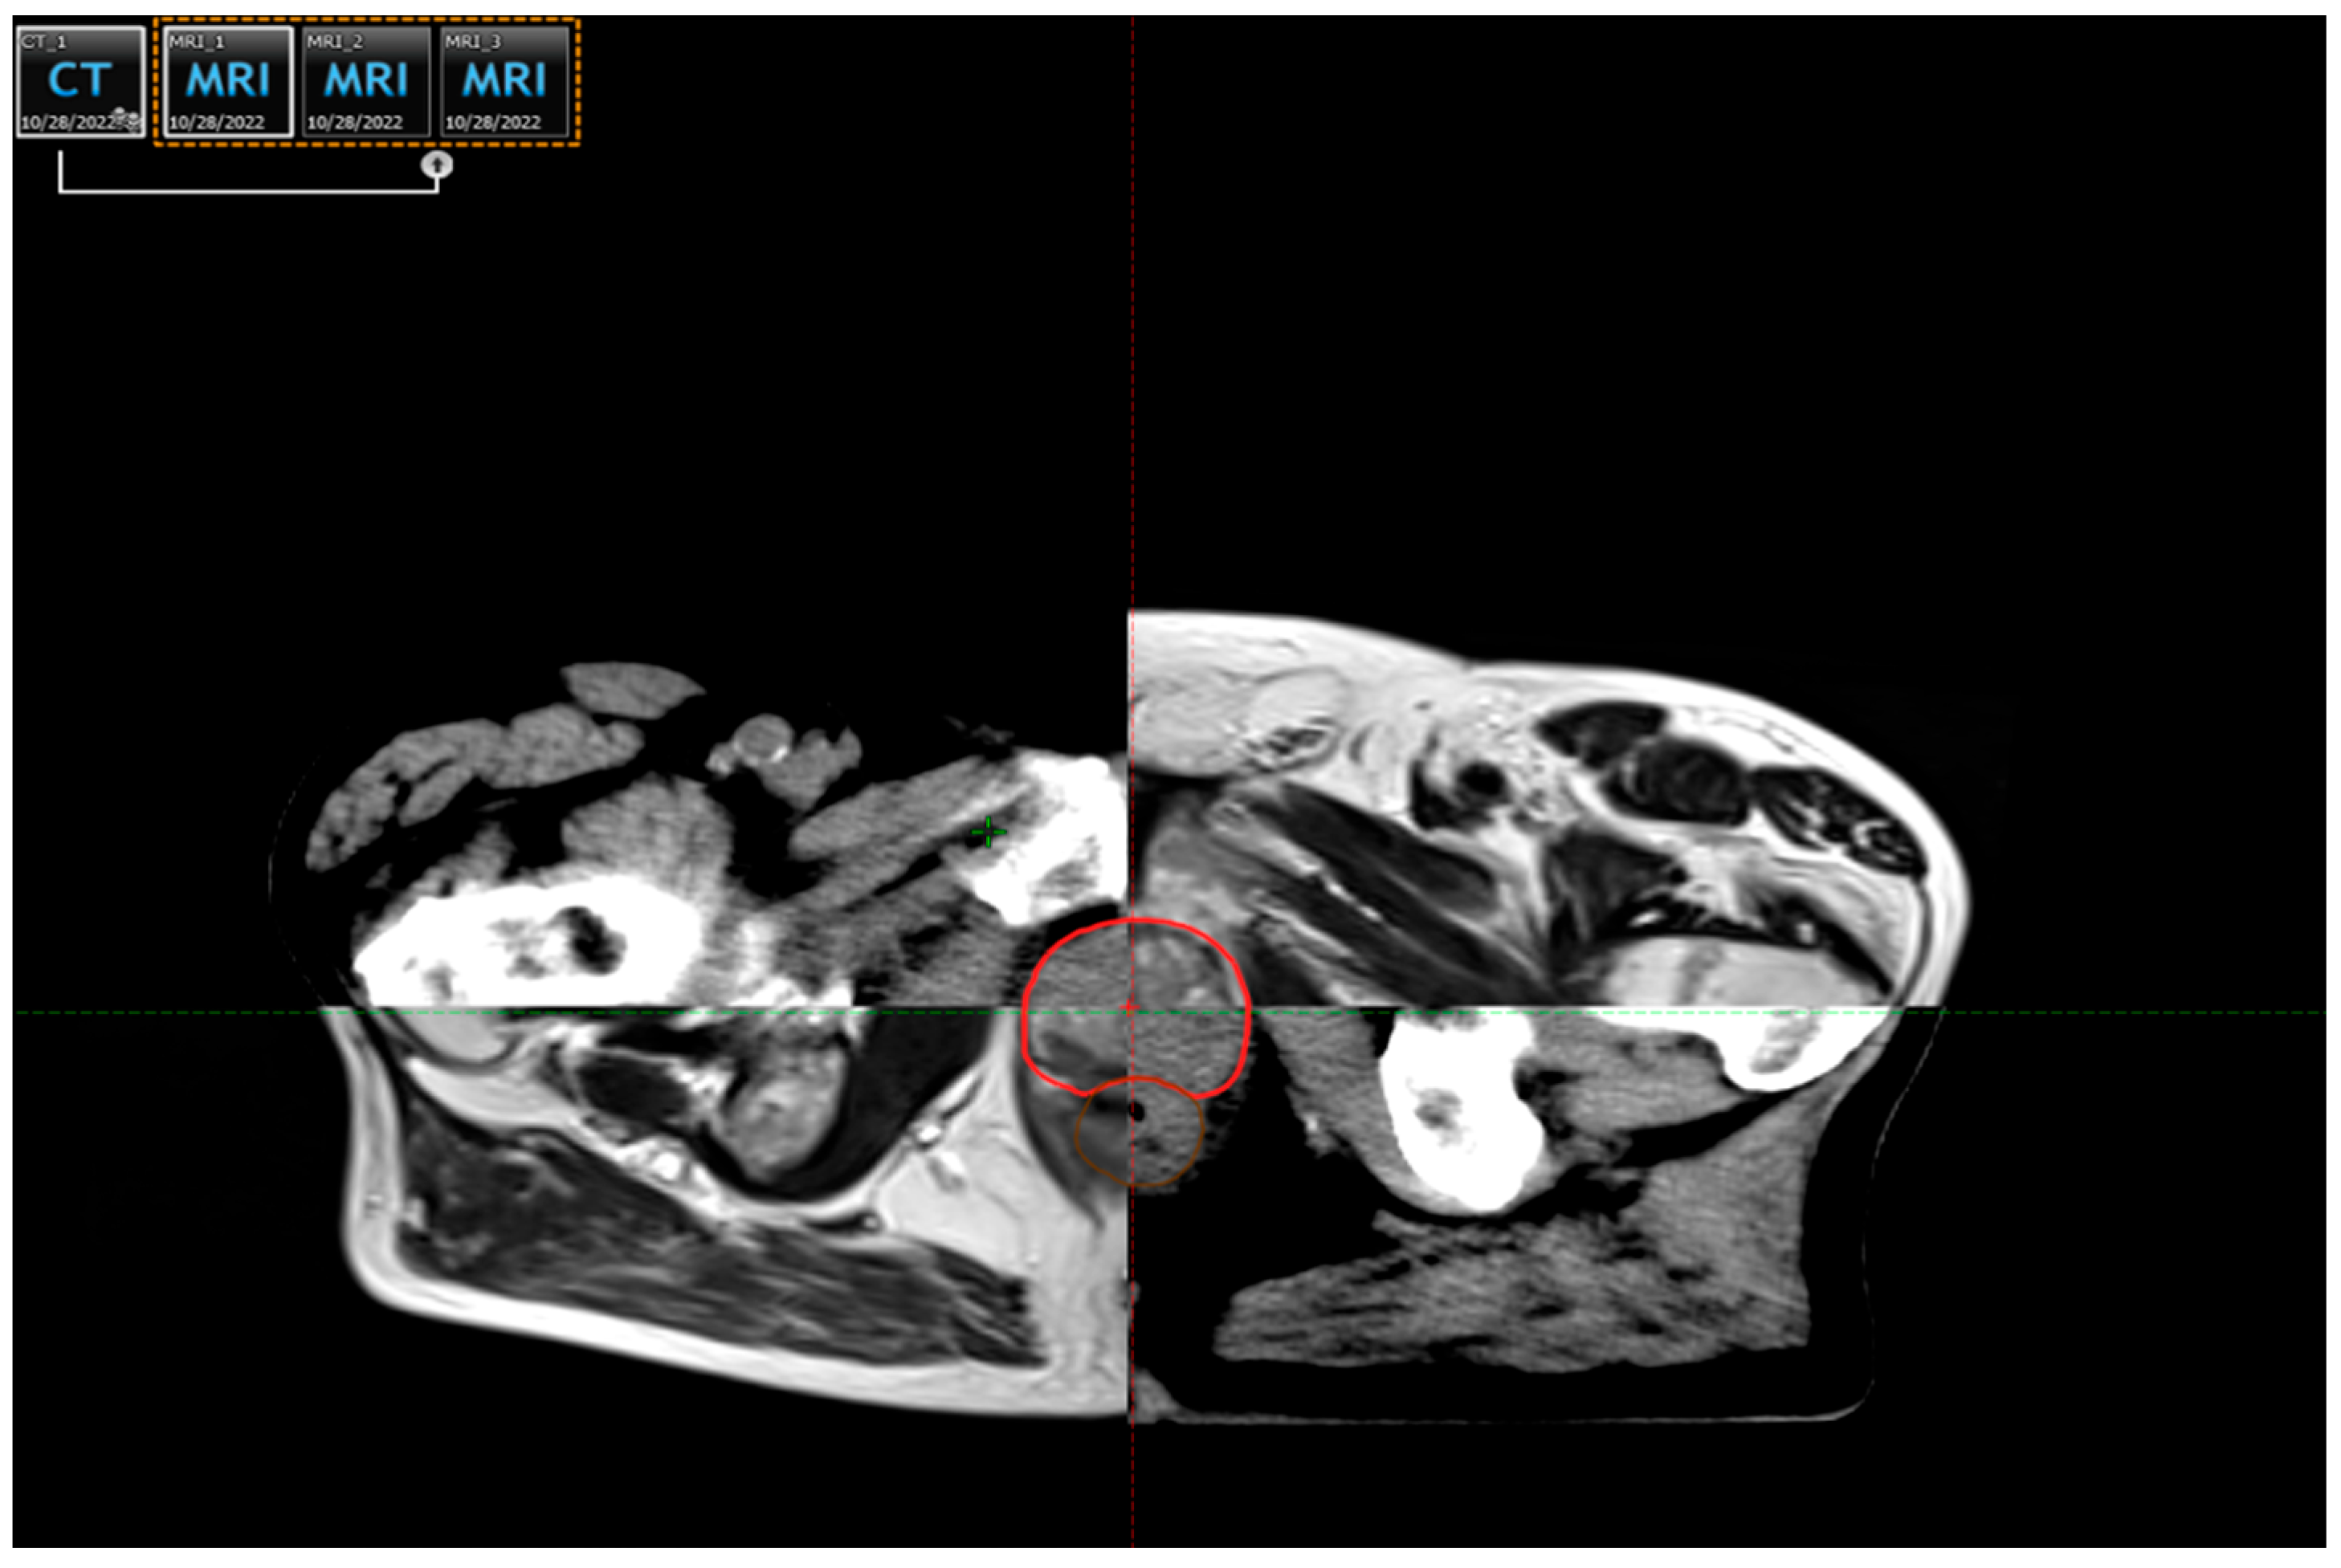

- Pereira, G.C.; Traughber, M.; Muzic, R.F., Jr. The Role of Imaging in Radiation Therapy Planning: Past, Present, and Future. Biomed. Res. Int. 2014, 2014, 231090. [Google Scholar] [CrossRef]